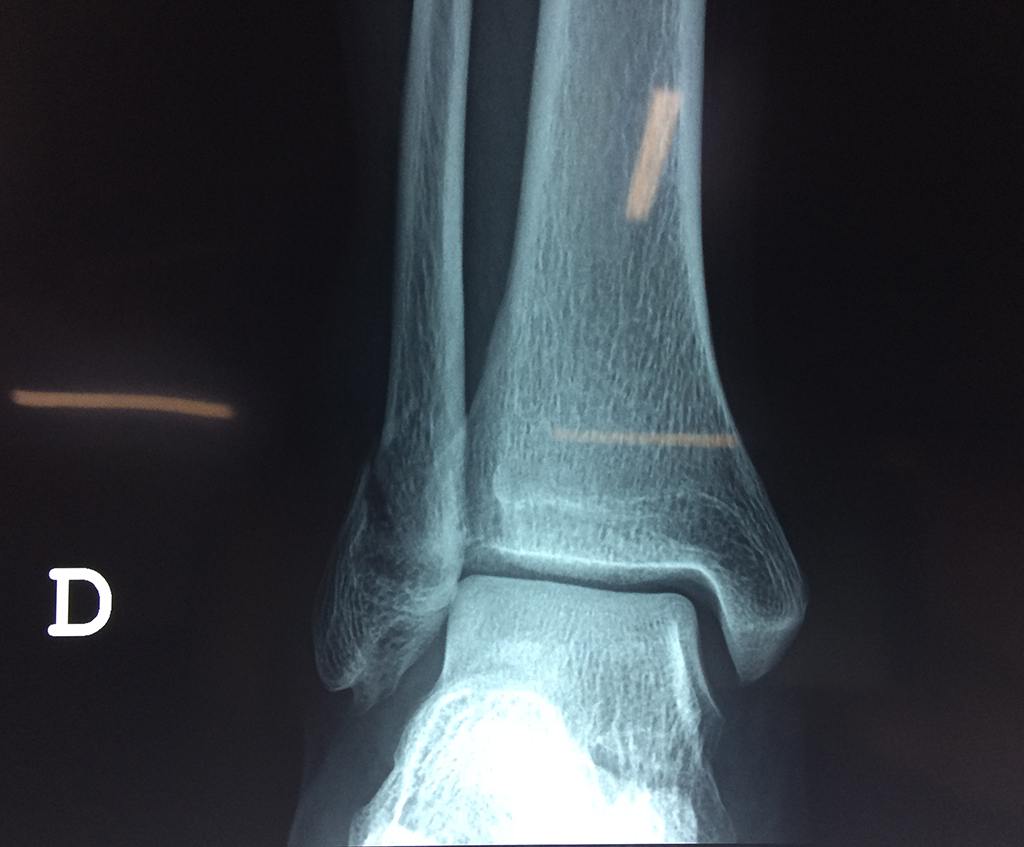

Una fractura de tobillo es la rotura de uno o más de los huesos del tobillo. Estas fracturas pueden ser:

Algunas fracturas de tobillo pueden requerir cirugía si:

- Los extremos de los huesos están desalineados entre sí (desplazados).

- La fractura se extiende hasta la articulación del tobillo (fractura intra-articular).